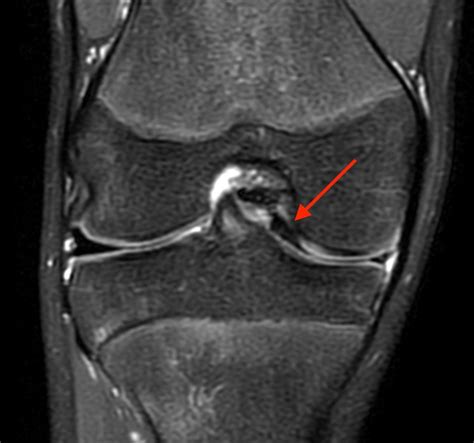

A Bucket Handle Meniscus Tear is a specific type of meniscus tear where a longitudinal tear occurs, causing a portion of the meniscus to displace and flip into the joint space. This displacement can resemble the handle of a bucket, hence the name. This type of tear is often more severe than other types of meniscus tears and can lead to significant knee instability and pain.

• Imaging Tests: Magnetic Resonance Imaging (MRI) is the gold standard for diagnosing meniscus tears. It provides detailed images of the knee joint, allowing for accurate identification of the tear.